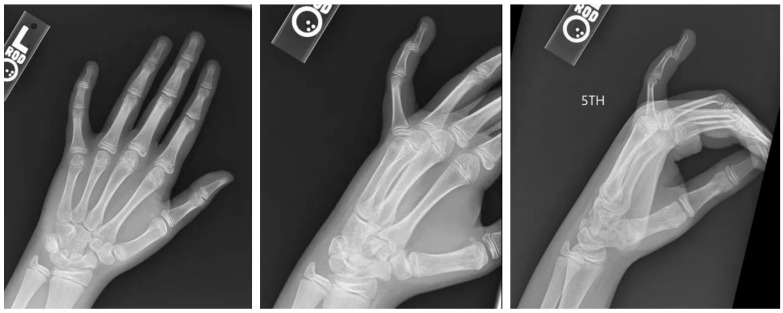

手指损伤在儿科患者中很常见,保守治疗通常愈合良好。然而,罕见的骨折类型涉及明显的移位和物理损伤,如本例所述,需要专门的手术干预,以确保适当的愈合和防止长期并发症。病例介绍:一名12岁的女性,以左手为主,表现为左第五指过伸后的远端指间关节疼痛、肿胀和畸形。最初的x线片显示掌侧移位的关节内骨折伴物理受累,经计算机断层扫描(CT)成像证实。保守治疗与闭合复位和夹板未能达到适当的对准。手术干预通过背侧入路进行,利用ORIF与k针固定来恢复关节一致性并确保解剖对准。结果:术后随访显示满意的愈合,保持复位,疼痛缓解,无并发症。患者以最小的僵硬度恢复了手指的功能使用,生长板在恢复期间未受累。讨论:本病例强调了先进影像学、早期转诊和量身定制的手术干预对罕见槌状骨折伴掌侧移位和物理损伤的重要性。在这个复杂的病例中,ORIF提供了可靠的稳定和最佳的结果。结论:掌侧移位的Salter-Harris III型DIP关节骨折是儿科患者罕见且具有挑战性的损伤。该病例强调了ORIF在获得成功结果中的作用,并强调了精确复位和稳定以防止长期并发症的重要性。

Introduction: Finger injuries are common in pediatric patients and typically heal well with conservative management. However, rare fracture patterns involving significant displacement and physeal injury, such as the one described in this case, require specialized surgical intervention to ensure proper healing and prevent long-term complications. Case Presentation: A 12-year-old left-hand-dominant female presented with pain, swelling, and deformity at the distal interphalangeal (DIP) joint following hyperextension of the left fifth digit. Initial radiographs revealed a volar displaced intra-articular fracture with physis involvement, confirmed by computed tomography (CT) imaging. Conservative management with closed reduction and splinting failed to achieve adequate alignment. Surgical intervention was performed via a dorsal approach, utilizing ORIF with K-wire fixation to restore joint congruity and ensure anatomic alignment. Outcomes: Postoperative follow-up demonstrated satisfactory healing, maintained reduction, and resolution of pain with no complications. The patient regained functional use of the digit with minimal stiffness, and the growth plate remained uninvolved during the recovery period. Discussion: This case underscores the importance of advanced imaging, early referral, and tailored surgical intervention for rare mallet fractures involving volar displacement and physeal injury. ORIF provided reliable stabilization and optimal outcomes in this complex case. Conclusions: Volar displaced Salter-Harris III fractures of the DIP joint are rare and challenging injuries in pediatric patients. This case highlights the role of ORIF in achieving successful outcomes and emphasizes the importance of precise reduction and stabilization to prevent long-term complications.